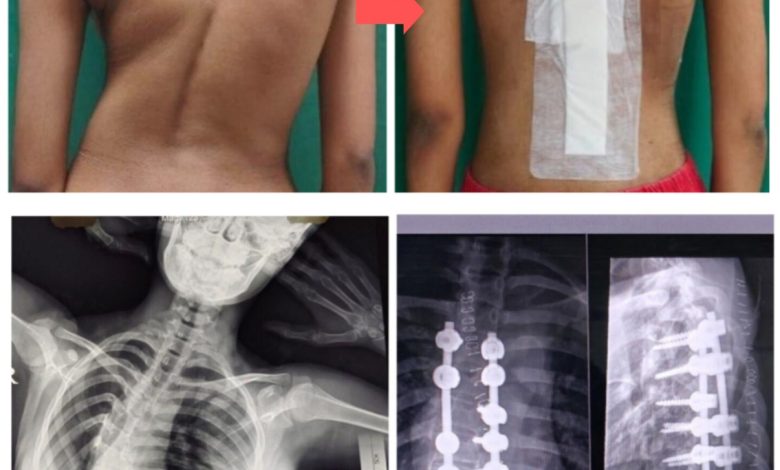

भोपाल। मध्य भारत में उन्नत चिकित्सा सेवाओं का केंद्र बनता जा रहा एम्स भोपाल अब गंभीर रीढ़ की हड्डी की बीमारियों, खासकर पीडियाट्रिक स्पाइनल डिफॉर्मिटी जैसे मामलों में भी आशा की किरण बन चुका है। हाल ही में, एम्स भोपाल में एक 14 वर्षीय बच्चे की गंभीर स्कोलियोसिस (Scoliosis) — अर्थात रीढ़ की हड्डी में असामान्य रूप से अत्यधिक टेढ़ापन — का सफल ऑपरेशन किया गया।

यह जटिल और उच्च जोखिम वाली स्पाइन सर्जरी संस्थान के कार्यपालक निदेशक प्रो. (डॉ.) अजय सिंह के मार्गदर्शन में, विशेषज्ञ डॉक्टरों की टीम द्वारा की गई। सर्जरी के लिए नेविगेशन तकनीक और अत्याधुनिक 3D CT इमेजिंग का उपयोग किया गया, जिससे न केवल ऑपरेशन की सटीकता बढ़ी, बल्कि मरीज को भी बेहतर और तेज़ रिकवरी मिली।

डॉ. वी. के. वर्मा के नेतृत्व में इस सर्जरी को अंजाम दिया गया, जिसमें एनेस्थीसिया विशेषज्ञ डॉ. शिखा जैन की भूमिका भी अहम रही। सर्जरी के बाद मरीज की स्थिति पूरी तरह स्थिर है और उसकी लंबाई में लगभग 2 सेंटीमीटर की वृद्धि भी देखी गई, जो इस सर्जरी की सफलता का प्रत्यक्ष प्रमाण है।